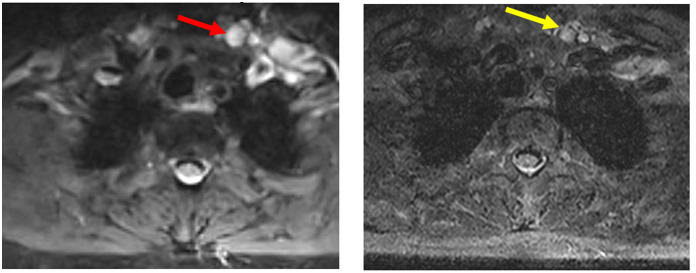

3.     Biến đổi trên chẩn đoán hình ảnh (trước và sau điều trị)

Hình ảnh MRI cổ: Hình hạch thượng đòn trái giảm kích thước sau 3 tháng điều trị, từ đường kính 10 mm (mũi tên đỏ) xuống còn 7mm (mũi tên vàng).